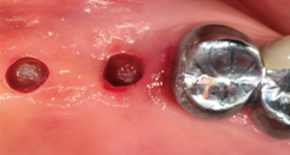

1. Preoperative

2. Body preparation